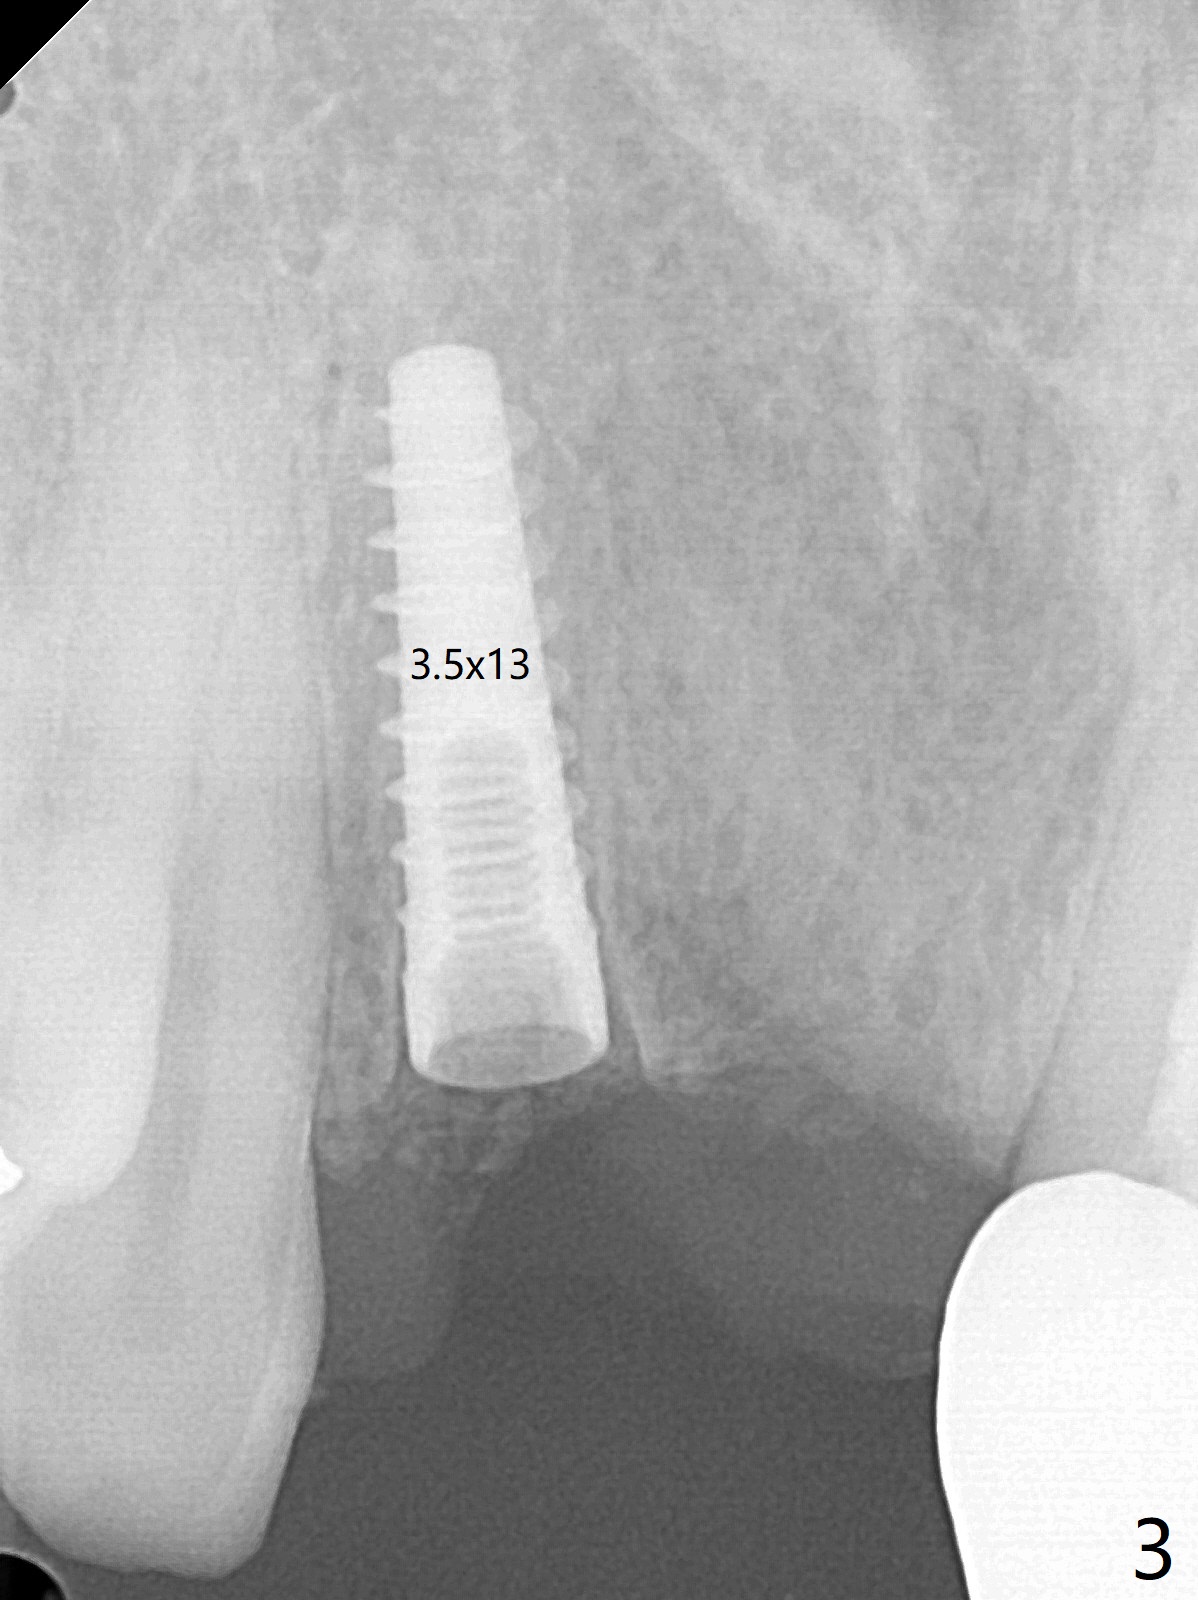

拆除部分桥发现:中,侧切牙牙龈红肿(图一),不利于切口和伤口愈合。不过还是在中切牙区切开,牙龈相当厚,有利于今后牙龈形成凹陷和乳头。坏消息是近远中距离太短,不利于植牙以及今后局部卫生维护,所以决定只在侧切牙种植(图二,三),完成钻洞后,颊侧根尖穿孔植骨,然后植入植体,即刻放置修复基台(图四 (*:牙龈乳头)),暴露基台牙龈缘,制作临时悬臂桥 (图五),两个中切牙牙冠长度差不多,插入临时桥时颊侧牙龈乳头基本形成(图六:*),缝合前颊侧,腭侧牙龈瓣下放置粘性骨块(图七,八:* )和PRF膜(图七:^)。最后使用牙周敷料。但愿术后牙龈炎症消失,形成良好牙龈乳头和pontic concavity。 其实由于口腔卫生习惯,术后十七天颊侧牙龈仍红肿(图九),而腭侧正常。如果口腔卫生改善而红肿依然存在,让实验室制作临时桥。术后一个月颊侧牙龈红肿好些(图十),好像骨粉丢失少许,可能与水枪使用有关。右上1牙冠显得太短(*)。也太肥大,因为右上1切缘太颊侧,与左上1对比(图十一:*)。由于颊侧牙龈(图十二:B)术中推向颊侧,与腭侧(P)牙龈之间放置大量粘性骨粉,术后一个月骨粉(<)形成牙龈,形成凹陷。颊侧萎缩不再明显了。右上1牙冠颈部多加些树脂,牙齿就显得长的多(图十三:箭头)。与侧切牙之间颈部故意留下间隙(*),让牙龈入位(空箭头),形成龈乳头。当右上1临时牙冠切缘(图十四:*)移到腭侧,外形改观不少。下次改善侧切牙唇侧。术后两个月三个星期牙龈红肿好像减轻,牙龈没有进入切牙间隙,干脆用树脂关闭(图十五:> <)。下次减少侧切牙切缘(^),适当增加中切牙长度(上提牙龈)。术后3.5个月植体好像整合,基台完全就位(图十六)。术后3.5个月Pontic凹陷形成,但是1,2之间龈乳头始终无法形成(图十七)。以后类似病例应该多种植一个。此例草率取模,可能需要临时粘固,观察植体近中颊侧所谓瘘道,必要刮治。由于比色不佳,需要实验室颜色更改,病人强化卫生,术后七个月,永久性牙冠粘固前,局部牙龈健康(图十八)。